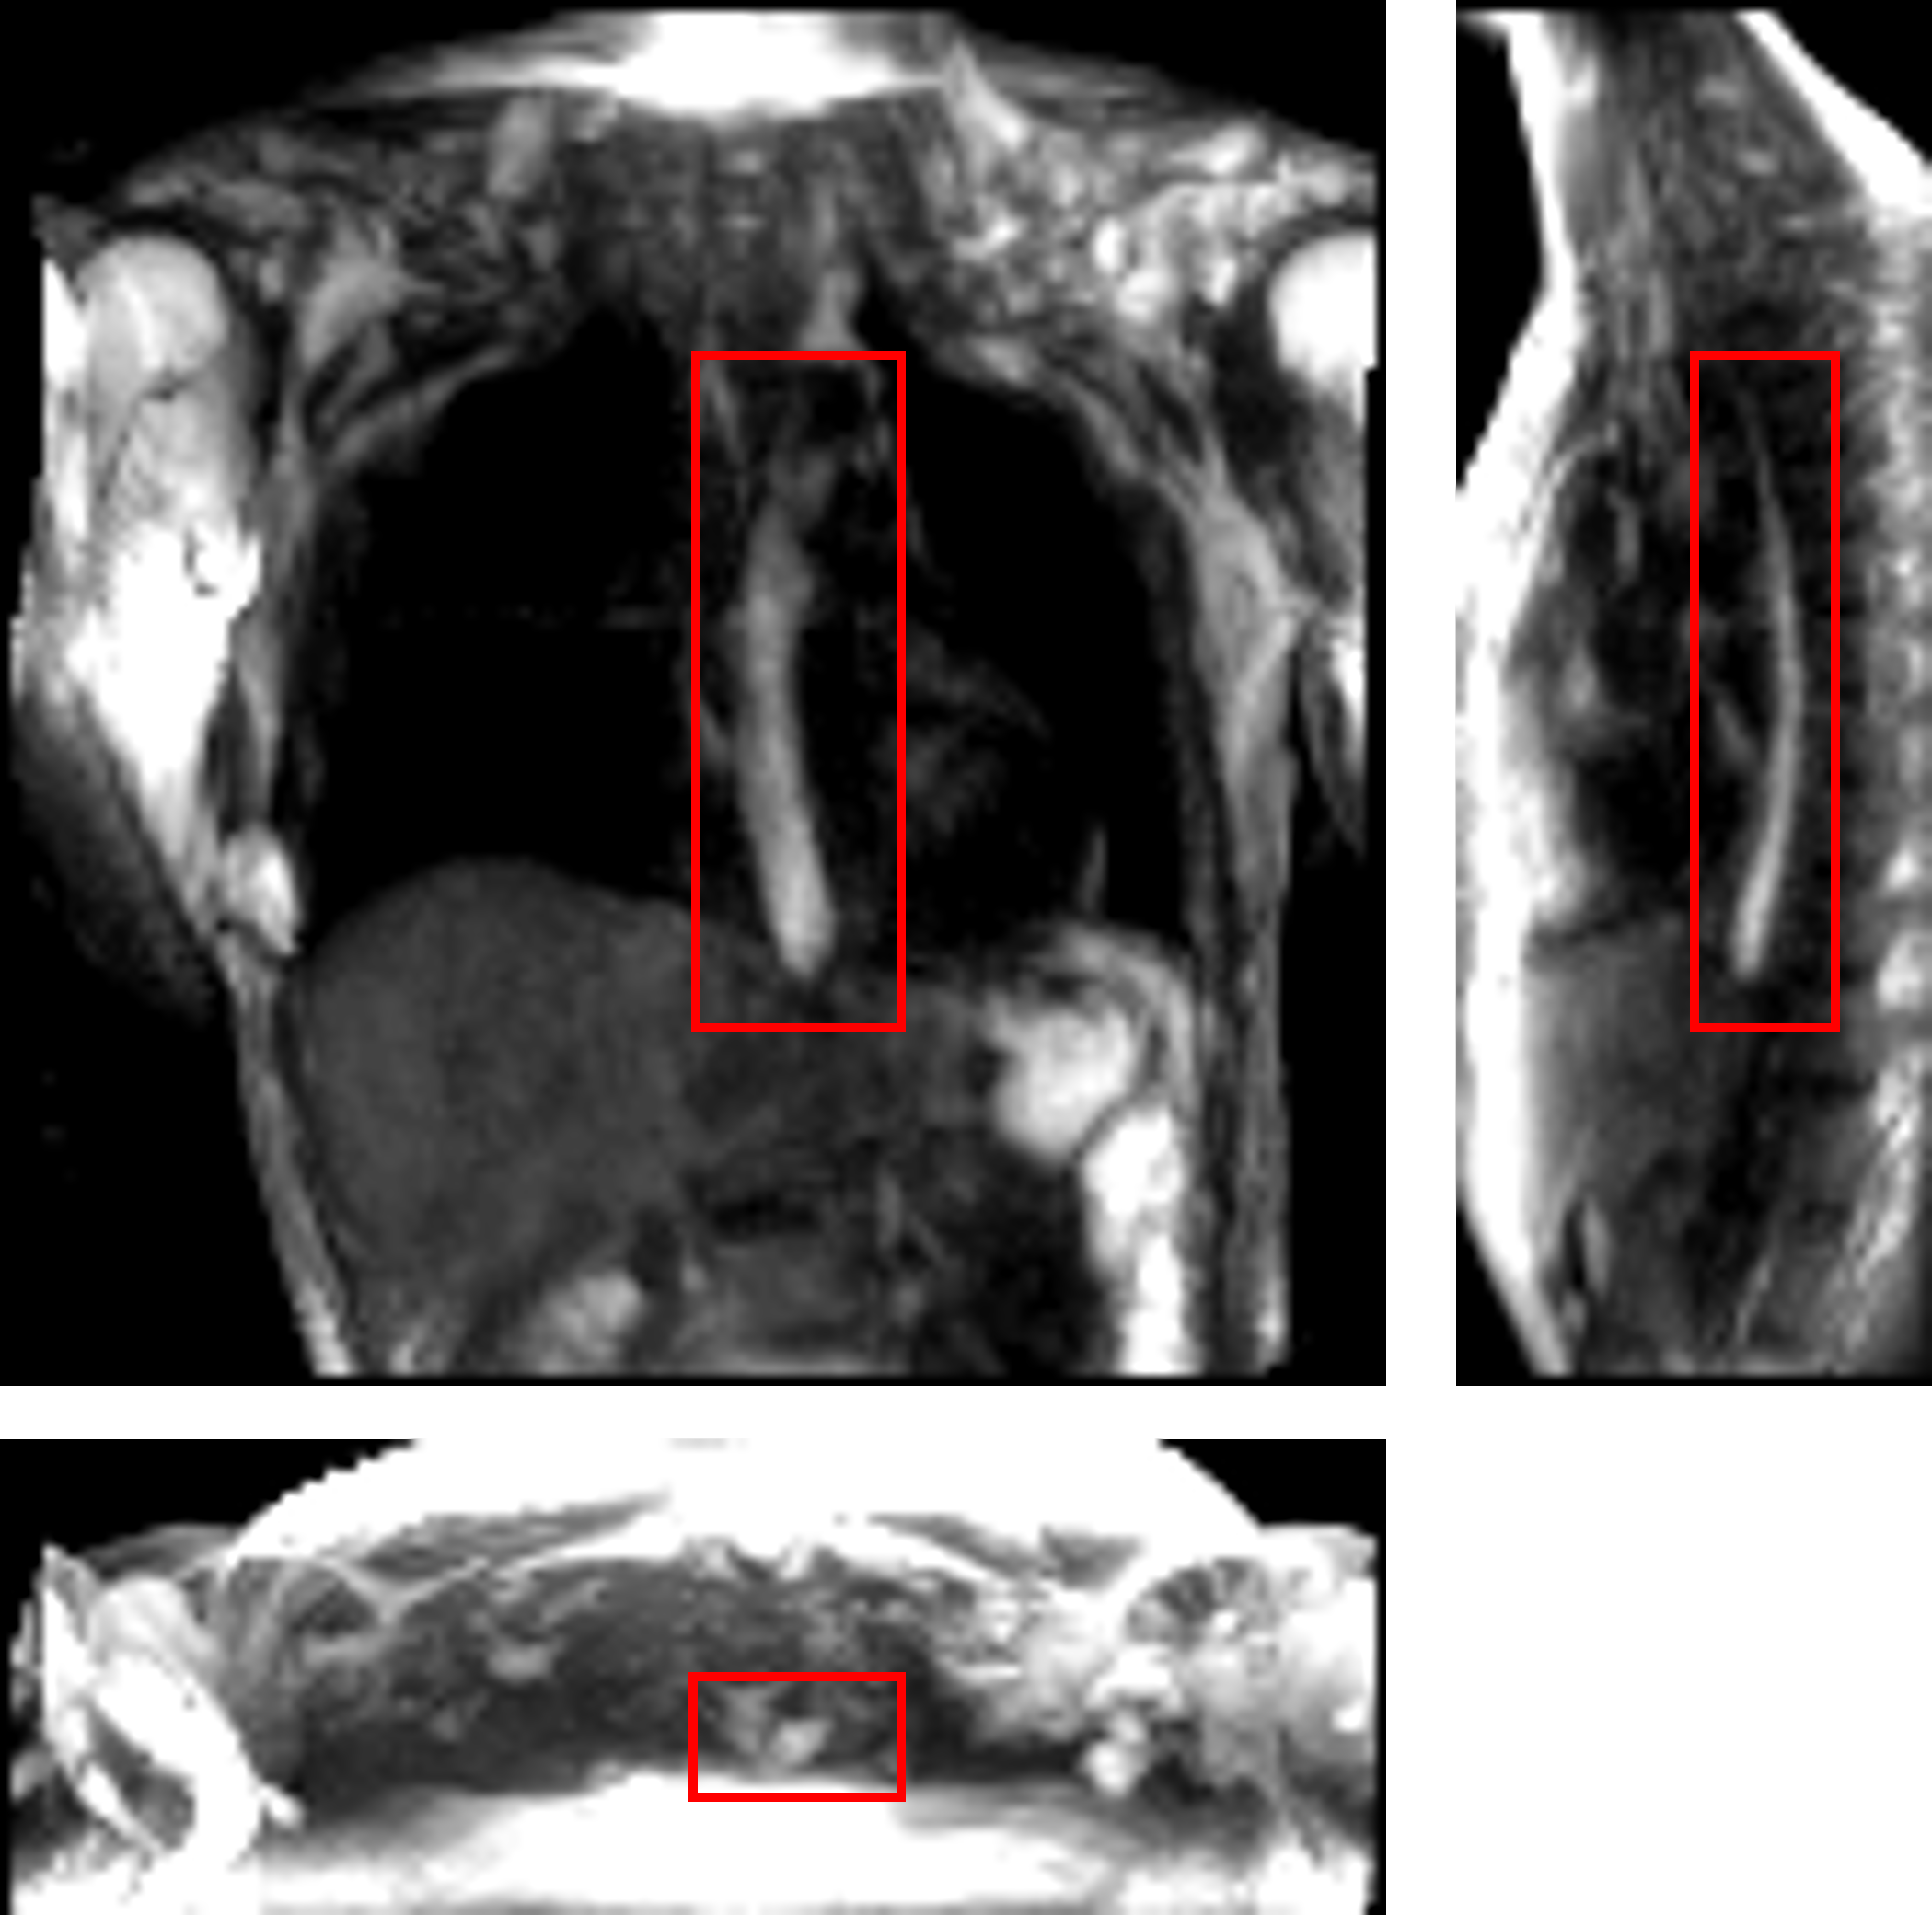

Imaging was performed at 1.5 T (Aera, Siemens, Germany) using a 3D MR angiography sequence (TWIST, Siemens, Germany) designed for contrast-enhanced cardiac imaging applications which was adapted to be used for esophageal imaging using pineapple juice as an oral contrast agent. Sequence parameters included (3.25 spatial / 1.17 s temporal resolution, (416 coronal field of view, 0.78 ms echo time, 2.36 ms repetition time, tip angle, 620 Hz/pixel bandwidth, 6/8 partial Fourier acquisition, R=2 GRAPPA acceleration, central size / outer density view sharing. A 4-channel cardiac coil was used for image acquisition, placed on the upper torso surface. To improve image conspicuity of the juice bolus, pineapple juice (100, Costa Rica) was reduced to a volume factor of 0.48 (i.e. 52 volume removed) through gradual heating without boiling. By doing so, the T1 of the juice at 1.5 T was reduced from 265 ms (raw / non-volume reduced juice) to 76 ms (volume-reduced juice), as measured by variable flip angle signal fit. A healthy volunteer (37 year old male) was given 20 ml of the volume-reduced pineapple juice to swallow during image acquisition. The juice was administered via a plastic tube and syringe controlled by the scan subject. The subject was instructed to swallow by voice command from the scan operator, given 10 seconds after the start of image acquisition, with 75 seconds of imaging performed to capture complete esophageal transit. To visualize the bolus transport, maximum intensity projections were created. Figure 1 shows an instant during bolus transport on three perpendicular slices.

The MRI output consisted of a cuboid wherein voxels in a Cartesian coordinate system had different magnitudes of intensity. The temporal resolution of the dynamic MRI (1.17 second) determined the number of images with the bolus seen within the esophagus; 7 time instants in this study. The typical length of an adult esophagus is 18 - 25 cm [27]. The average velocity of a normal peristalsis is approximately 3.3 cm/s [28]. Thus, an average swallow sequence usually takes 5 - 8 seconds. Therefore, temporal resolutions similar to what we used in our analysis typically result in 5 - 8 images. Although this temporal resolution is not comparable to fluoroscopy, the detailed three-dimensional geometry of the bolus in MRI leads to better prediction of velocity and intrabolus pressure resulting in better prediction of esophageal wall properties. The bolus was manually segmented for the 7 time instants, a few of which are shown in Figure 2. The segmentation assigned a value of 1 and 0 to each voxel that lay inside and outside the bolus, respectively. The image segmentation was performed using the open-source software ITK-SNAP [29]. With improved MR imaging and better temporal resolution, manual image segmentation might not be feasible and more sophisticated automated segmentation techniques might be necessary. We have described a deep learning based automated segmentation approach called 3D-U-Net [30] in the Appendix which was fine-tuned for this application.